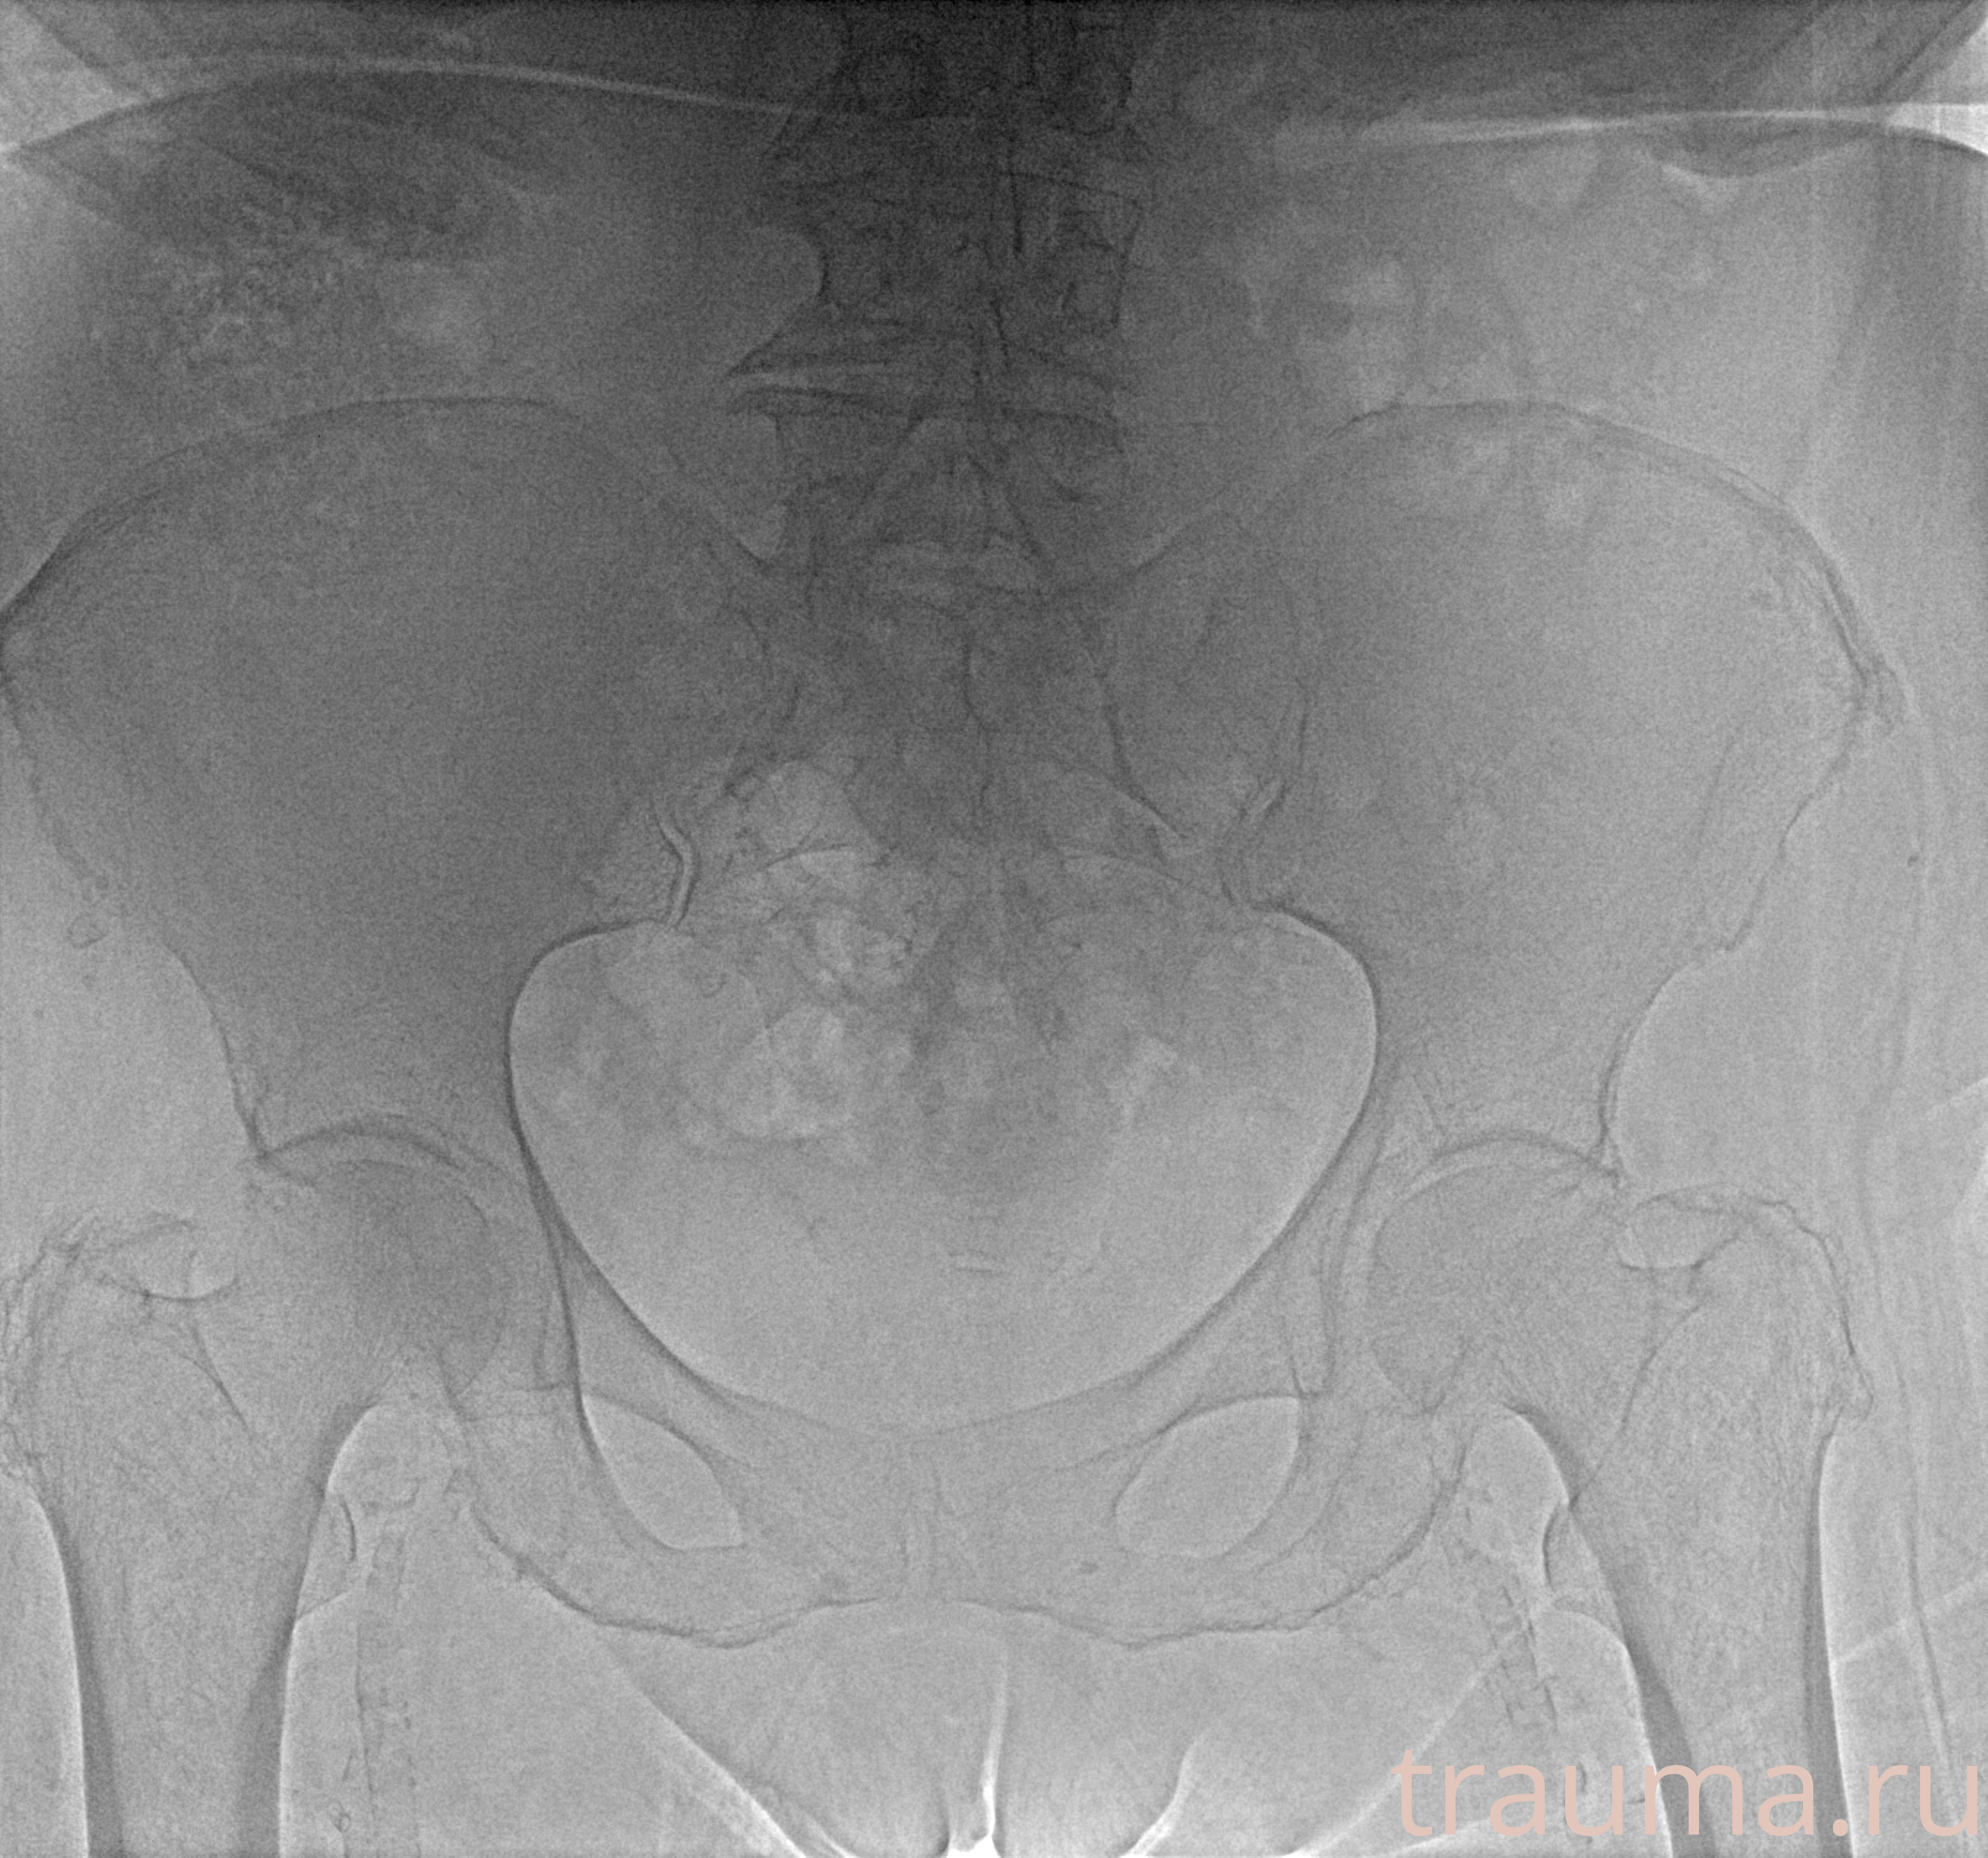

Рентген на дому: по вашему адресу приезжает врач-рентгенолог, травматолог-ортопед с мобильным рентгеновским аппаратом, проводит диагностику травмы или заболевания, делает необходимые рентгенограммы, дает рекомендации по дальнейшему лечению. Получить качественные снимки в домашних условиях возможно благодаря уникальной методике, разработанной МосРентген Центром для института  Склифосовского